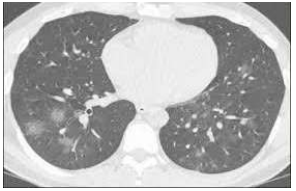

Um homem de 64 anos de idade, diabético, em uso regular de suas medicações, procurou um pronto-socorro na cidade de São Paulo no dia 24 de junho de 2020, referindo que, há seis dias, vinha com dor de garganta e diarreia, sendo que, há três dias, iniciou tosse seca. Ao ser questionado pelo médico, ainda relatou que teve perda de apetite dois dias antes do início dos sintomas. O paciente levou consigo hemograma e urina tipo 1 de uma passagem que tivera, há dois dias, em outro serviço médico, com resultados normais. Negou tabagismo, etilismo ou exposição a trabalhos que, ao longo da vida, pudessem ter desencadeado doenças profissionais. Ao exame físico, apresentava bom nível de consciência,saturação de O2 de 85% em ar ambiente e de 97% com cateter de O2 2L/min., FC de 95 bpm, 37,8 ⁰C de temperatura, PA de 145 x 90 mmHg, FR de 18 irpm, obesidade grau II e encontrava-se prostrado, desidratado, corado, anictérico e com movimentos respiratórios amplos. Aparelho cardiovascular com bulhas rítmicas, sem sopro, e tempo de enchimento capilar igual a 4 s. Aparelho respiratório com murmúrio vesicular difuso mais evidente em bases pulmonares, bilateralmente. Som pulmonar claro. Abdome com hiperdinamia à ausculta, ausência de massas à palpação superficial e profunda e dor difusa discreta. Exames atuais com Hb 16, Ht 54, leucócitos 12.000 (73% neutrófilos e 25% linfócitos), plaquetas 285.000, Na 158, K 2.5, Mg 1.9, ureia 80 e creatinina 2.5. Gasometria em ar ambiente com pH 7.3, PaO2 58 mmHg, PaCO2 40 mmHg, BE –4, lactato arterial 1.25, bicarbonato 17, CPK 350, ALT 70 e AST 60. Urina I com densidade 1.030, proteína +++, glicose +++, leucócitos 250.000 e eritrócitos 500.000. Realizou, também, a tomografia de tórax mostrada a seguir.